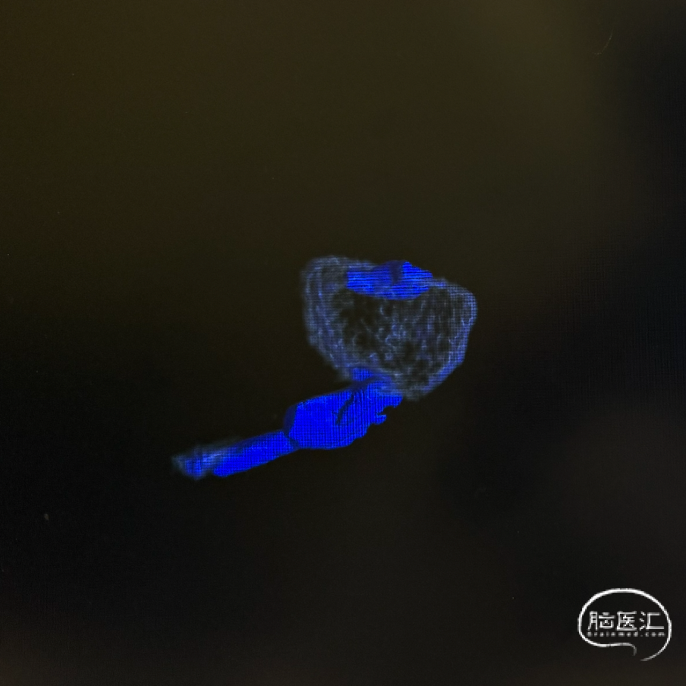

三维旋转图像:左侧大脑中动脉早额支起始部囊性动脉瘤。

术后三维重建及WEB™融合后图像,可见WEB™贴壁良好。

WEB™释放的实时评估:在成角部位,装置展开易受血流冲击影响。需通过多角度造影动态观察WEB™形态,重点确认瘤颈覆盖是否完全、尾端是否充分展开。本例通过反复调整,最终实现装置稳定贴壁,术后利用西门子自带多容积三维重建,分析扰流装置的位置,证实了技术操作的可靠性。